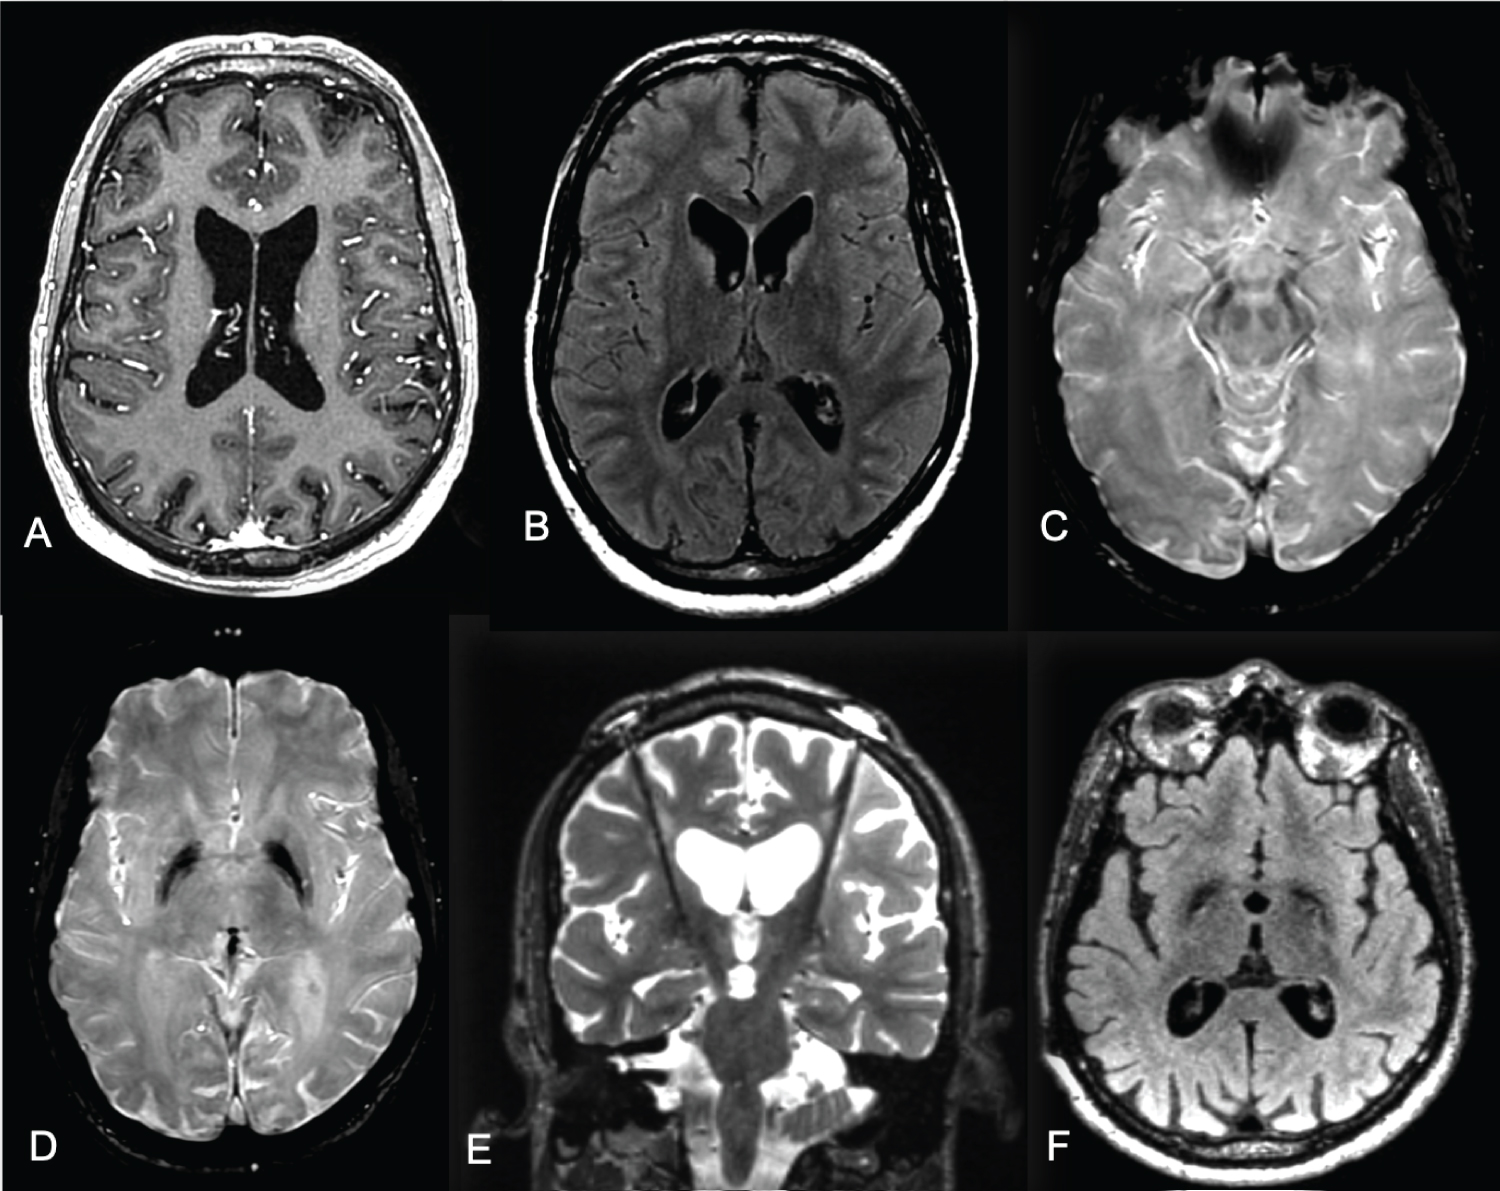

Brain magnetic resonance imaging (Figure 1) demonstrated atrophy of the head of caudate nuclei and abnormal iron deposition in the nigra substance and globus pallidus. MTS was genetically confirmed by identifying hemizygosis in the TIMM8A gene (ChrX variant 100.603.526) (Translocase of Inner Mitochondrial Membrane 8, Yeast, Homolog of, OMIM*300356) through exome sequencing. There is not reported family history of neurological disease.

Figure 1: Brain MRI in axial T1 (A), axial FLAIR (B) and axial SWI (C and D) sequences showing brain atrophy more evident of the parietal lobes, atrophy of the head of caudate nuclei with abnormal iron deposition in the nigra substance and globus pallidus. Brain MRI coronal T2 (E) and axial FLAIR sequences (F) with deep brain stimulation electrodes at globus pallidus internus. View Figure 1

DBS GPI was performed with stereotaxic computed tomography guidance under general anesthesia. Electrophysiology was used to identify the target regions and guide DBS electrode placement. There was no evidence of microlesion effect due to electrode insertion during the postoperative period, and the maximum DBS benefit occurred 6 months post-surgery. Brain MRI (Figure 1) represents the postoperative imaging of Gpi DBS electrode localization.